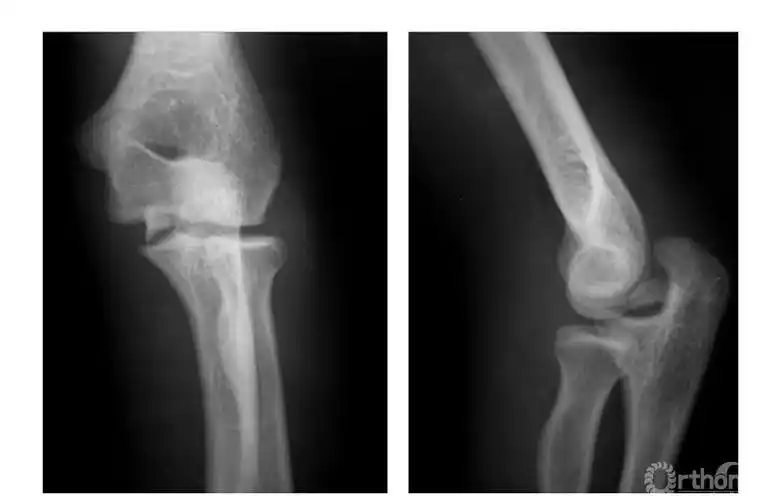

骨科常见疾病x线解析之肱骨内上髁骨折